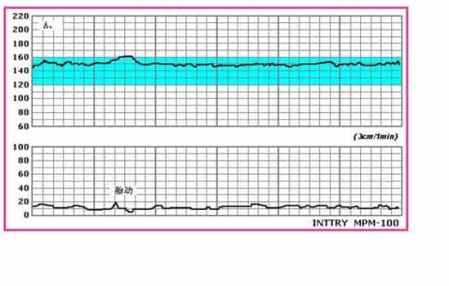

胎心监护图上会有两条曲线,一条记录的是胎心率的变化,另外一条记录的是宫缩情况,格子横向代表时间,竖向达表次数。正常情况下胎心率都会保持在120~160次/分钟,胎儿活动的时要比休息的时胎心率加快(每分钟至少快15下),并且持续至少15秒,这种正常的情况被成为“胎心监护反应型”,这是每一位孕**都希望得到的结果。

1、20分钟内胎心基线是120至160次在无胎动的情况下是最好的,得满分大于160或小于120酌情扣分。

2、振幅是无胎动时胎心基线的波动幅度,10以上是满分,5-9次是1分。

3、胎动时胎心上升的次数要大于15次,从起点到最高点的次数。

4、胎动时胎心上升持续的时间要大于15秒,从起点到最高点的时间。

5、胎儿在20分钟内胎动的次数要大于3次。